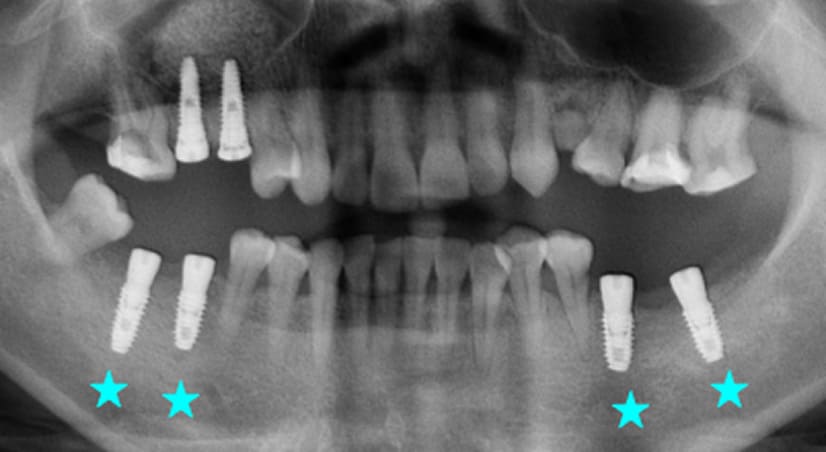

9年以上

-

种植体植入 2012年10月 -

随访:2年 2014年7月 -

随访:9年 2021年9月